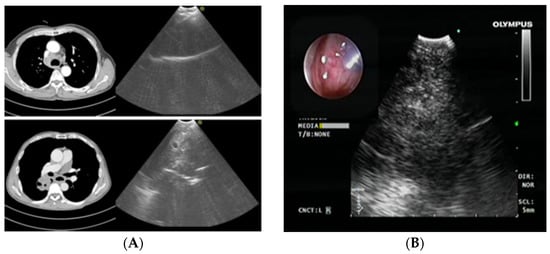

2.1. Cryobiopsy for Endoscopy Visible Tumor Lesions and Transbronchial Cryobiopsy for Peripheral Tumor Lesions—Application of Molecular Tests

2.2. Radial Probe—Endobronchial Ultrasound with a Guide Sheath in the Diagnosis of Peripheral Lung Lesions

RP-EBUS-GS—Guided Endobronchial Ultrasound in the Era of Molecular Testing of Tumor Tissue